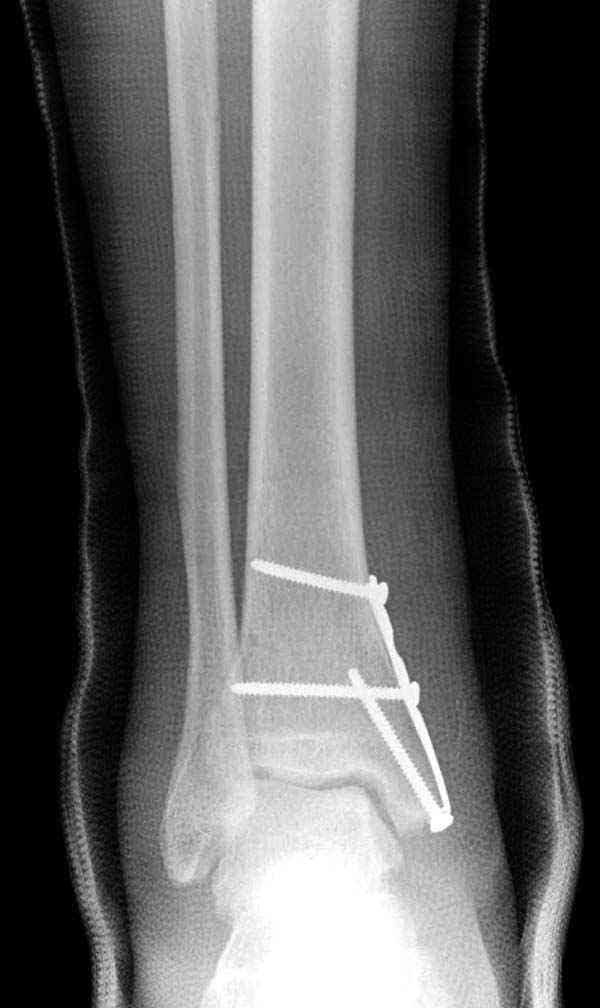

Внутренняя лодыжка

Вложение не в текстовом формате было извлечено…

Имя     : 2 Med mal fx Hook plate 00.JPG